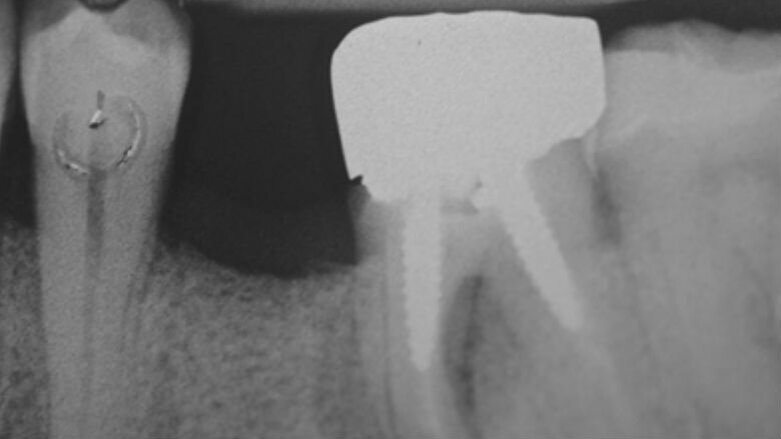

La rimozione delle suture è avvenuta a 7 giorni dall’intervento. Il paziente è stato controllato dopo ulteriori 21 giorni e ogni mese per i successivi 12 mesi (Fig. 3). Successivamente è stato richiamato per i controlli ogni 6 mesi. Il paziente non ha sofferto di alcuna complicanza post-operatoria. La guarigione completa della gengiva per seconda intenzione è avvenuta nell’arco dei 60 giorni successivi all’intervento. Sia ai controlli intermedi che al controllo a 24 mesi non si è osservata perdita del volume alveolare, né in senso verticale né in senso orizzontale (Figg. 4, 5).

Fig. 4 - a: spessore crestale a 8 mesi dalla chirurgia rigenerativa. b: radiografia endorale a 8 mesi, vi è un buon mantenimento del profilo crestale.

Fig. 5 - a: aspetto clinico del sito a 24 mesi dall’innesto, lo spessore crestale appare inalterato. b: radiografia endorale a 24 mesi. Anche l’altezza crestale appare conservata.